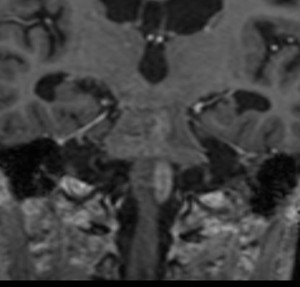

3歳の子どもの髄芽腫の放射線治療後に生じた脳萎縮

3歳の髄芽腫です。発症時から小脳表面や小脳橋角部を含めて転移がありました stage M2。化学療法で腫瘍はかなり縮小して,3歳7ヶ月まで頑張ってから,後頭窩照射 25.2グレイ14分割と脳脊髄照射 CSI 28.8グレイ16分割の放射線治療をしました。当時このような例では,脳脊髄照射 36グレイが標準治療でしたから,これでもかなり線量を落としました。

左側の画像は照射後4ヶ月目です。延髄の左側に放射線壊死が生じました。これは数ヶ月かかってゆっくり消褪しました。右側の画像は照射後1年くらいのものです。大脳白質にびまん性に萎縮性変化がみられます。典型的な放射線治療による白質萎縮です。この程度の線量でも脳壊死や全脳萎縮を生じない子どももいます。

放射線の副作用は同じ線量でも個人差がとても大きいです idiosyncrasy